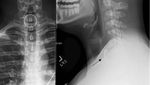

Seorang pria berusia 19 tahun di Albany, Amerika Serikat mengalami 'apes' tak sengaja menelan tutup botol besi saat bermain 'beer pong'. Karena tutup botol itu tersangkut, ia sampai kesulitan menelan dan mengalami gangguan pernapasan. (Foto: Cureus Journal)

Pemeriksaan menunjukkan tenggorokan pria tersebut mengalami peradangan. Dokter terpaksa harus melakukan operasi bedah untuk mengeluarkan tutup botol tersebut, karena berisiko memicu robekan atau perforasi (Foto: Cureus Journal)